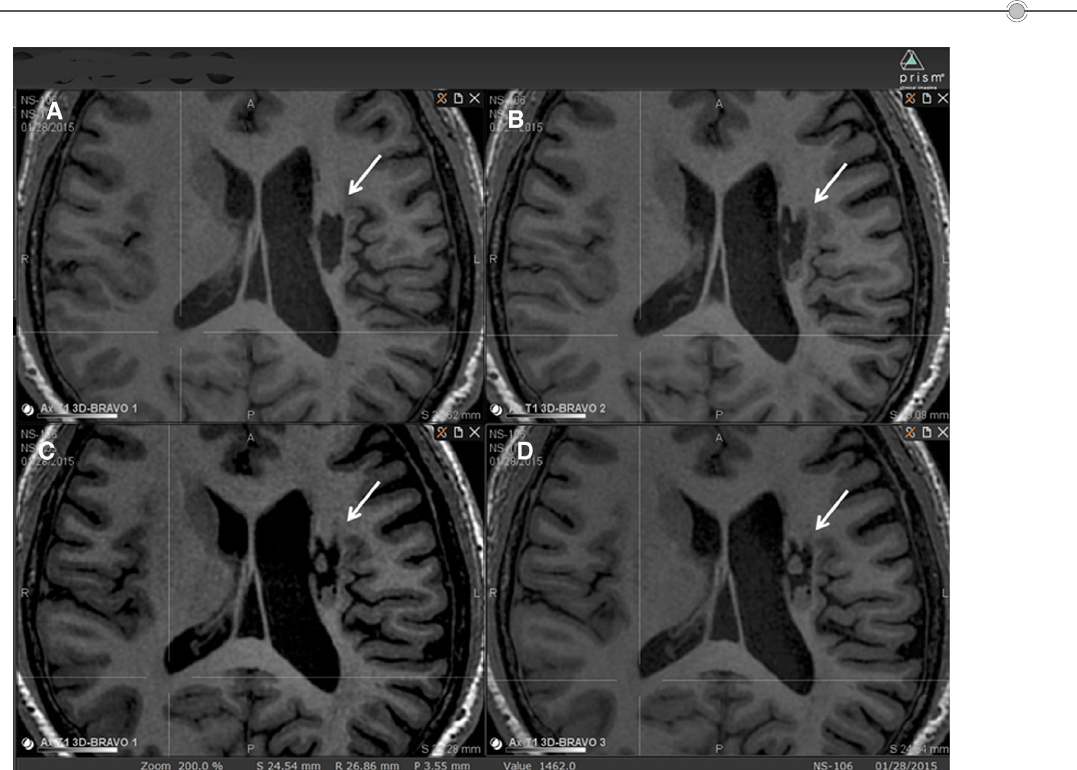

2019年6月,解放军总医院在《干细胞转化医学》(Stem Cells Translational Medicine)杂志上公布[3],干细胞移植有助于脑卒中偏瘫患者运动功能的恢复。9名年龄在30至65岁之间的偏瘫患者参与了这项临床研究,他们在中风后5-24个月接受人源神经干细胞NSI-566脑内移植(移植至脑内梗塞灶附近)。结果表明,人源神经干细胞NSI-566治疗偏瘫性脑卒中拥有一定的临床益处。

图片来源文献3